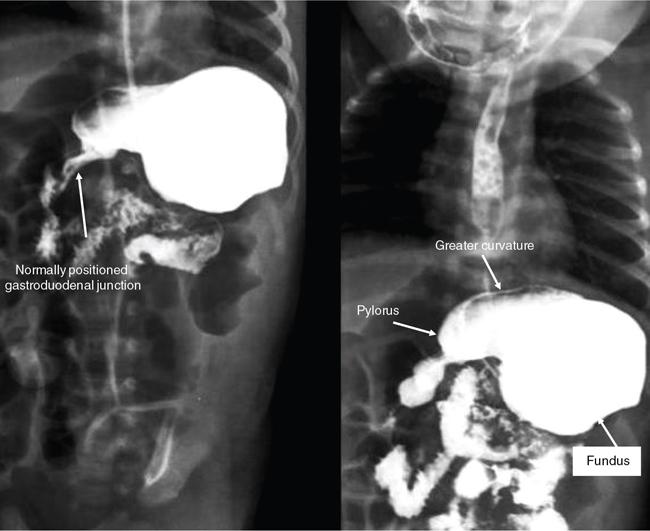

Swarup Nellore, Soumil Vyas, Ujwal Bhure, Ankit Jain, Richa Kothari, Daksh Mehta, Divya Kantesaria, Disha Lokhandwala, Karthik Ganesan The stomach is the most dilated portion of the gastrointestinal tract positioned between the oesophagus and the small intestine occupying the epigastrium, left hypochondrium and umbilical regions of the abdomen performing a multitude of functions including storage and mixing of food and controlling the passage of food into the intestine. Anatomically, the stomach is divided into the following parts (Fig. 8.2.1): the gastric cardia is the portion immediately adjoining the oesophageal opening into the stomach. The fundus is the dome-shaped part above the horizontal plane of the cardiac orifice which undergoes receptive relaxation and is the site of the autonomic pacemaker. The body is the largest part of the stomach extending from the cardiac orifice to the level of incisura angularis (notch like bend in the mid lesser curvature) containing majority of parietal cells (which secrete hydrochloric acid), chief cells (pepsinogen) and enterochromaffin-like cells (ECL). The pylorus is the tubular distal portion of the stomach which is further divided into the gastric antrum and pyloric canal. The pyloric antrum containing G-cells producing gastrin extends from the incisura angularis up to the pyloric sphincter which is an anatomical sphincter formed by concentric thickening of the circular muscle coat and encircles the narrow-slit like pyloric canal. The left dome of diaphragm and oesophagus lie superior to the stomach while the greater omentum and pancreas lie inferiorly. Spleen and liver lie on either side laterally while the transverse mesocolon is located inferolaterally. Diaphragm, greater omentum, left lobe of liver and anterior abdominal wall are anteriorly related to the stomach and contents of lesser sac including pancreas, spleen, splenic artery, transverse mesocolon, left kidney and adrenal gland lie posteriorly. The stomach is embryologically derived from the primitive foregut and is suspended anteriorly by the ventral mesogastrium and posteriorly by the dorsal mesogastrium. During development as the stomach rotates, the peritoneum grows and condenses to form perigastric ligaments, which contain blood vessels, lymphatics, lymph nodes, nerves and fat. The liver forms in the ventral mesogastrium, which develops into the falciform ligament, gastrohepatic ligament (GHL) and hepatoduodenal ligament (HDL). The spleen and pancreas form within the dorsal mesogastrium, which fuses with the posterior abdominal wall to form the gastrocolic ligament (GCL), gastrosplenic ligament (GSL) and splenorenal ligament (SRL). The perigastric ligaments are identified anatomically by the vessels contained in them (Fig. 8.2.2). The gastric cardia and lesser curvature of the stomach are attached to the inferior surface of liver by the lesser omentum by the gastrohepatic ligament respectively which contains the left and right gastric vessels. The inferior free edge of the gastrohepatic ligament extends inferiorly as the hepatoduodenal ligament between the porta hepatis and proximal duodenum gastrophrenic ligament extends between the stomach and the left hemidiaphragm. The gastrocolic ligament identified by the left and right gastroepiploic vessels, connects the greater curvature of the stomach to the anterior surface of the transverse colon. This ligament extends inferiorly as the greater omentum which is a double-layered peritoneum forming a drape anterior to the bowel loops. The gastrosplenic/lienogastric ligament bridges the posterolateral wall of the fundus and greater curvature along the proximal body of the stomach to the splenic hilum and contains the short gastric vessels. The gastrosplenic ligament is contiguous with the lienorenal ligament and both these structures constitute the lateral boundary of the lesser sac. Macroscopically the stomach shows a thick vascular mucosal lining in the form of longitudinal folds called gastric rugae. Microscopic layers of the stomach include mucosa, submucosa, muscularis externa and serosa. The mucosa includes surface mucus cells with simple columnar epithelium, gastric pits, gastric glands, lamina propria and muscularis mucosa. Submucosa includes connective tissue with submucosal Meissner’s plexus. Muscularis externa comprises three smooth muscle layers (longitudinal, circular and oblique) and Auerbach myenteric plexus. The outermost layer called serosa consists of loose connective tissue and visceral peritoneal lining. The arterial supply of stomach is constituted by the branches of celiac artery predominantly in the form of two anastomotic arcades along the lesser and greater curvature. Left gastric artery, a direct branch of the celiac trunk supplies the upper part of the lesser curvature while the lower part is supplied by the right gastric branch of the common hepatic artery arising at the upper border of pylorus. The left gastroepiploic artery, a branch of splenic artery, supplies the upper part of greater curvature and the inferior portion is supplied by the right gastroepiploic artery which is a branch of the gastroduodenal artery. The fundus additionally receives few small short gastric branches from the splenic artery. The veins follow the arteries in their nomenclature. Left and right gastric vein show direct drainage into the portal vein. The splenic vein derives flow from the short gastric and left gastroepiploic vein whereas the right gastroepiploic vein drains into the superior mesenteric vein. Pylorus can be surgically delineated by the prepyloric vein of Mayo lying on its anterior surface. Intrinsic nerve supply consists of the myenteric plexus of Auerbach and submucosal plexus of Meissner. Extrinsic nerve supply consists of sympathetic and parasympathetic components. Sympathetic nerve supply arises from T5 to T9 spinal cord segments supplying the celiac plexus via the greater splanchnic nerve. The plexuses then travel along the respective branches of celiac artery supplying the stomach. Parasympathetic nerve supply is derived from oesophageal plexus of vagus dividing into two vagal trunks. Right (posterior) vagus gives off the posterior gastric branch also called the criminal nerve of Grassi supplying the cardia and fundus of stomach. Right vagus then gives off a celiac branch and continues along lesser curvature of stomach as the posterior gastric nerve of Latarjet supplying the antrum, body and pylorus. Left (anterior) vagus gives off a hepatic branch then continues along the lesser curvature as the anterior nerve of Latarjet supplying the antrum, body and pylorus. Crow’s feet innervation to antropyloric area are important surgical landmarks preserved during highly selective vagotomy receiving branches from both major nerve trunks (anterior and posterior) at the incisura angularis. Anatomical lymphatic drainage is divided into three areas. Area I is the superior two-thirds of stomach draining via the nodes along left and right gastric vessels into the aortic nodes. Area II includes the right two-thirds of the inferior one-third which drains through the nodes along right gastroepiploic vessels via the subpyloric nodes into aortic nodes. Area III includes left one-third of greater curvature draining via short gastric and splenic nodes into suprapancreatic nodes and ultimately into aortic nodes. Gastric lymph node stations are divided into 4 levels with 16 lymph node stations: Paraesophageal nodes below the diaphragmatic hiatus (17) and above the diaphragmatic hiatus (18) are also included. The stomach first appears as a fusiform dilatation in the distal endodermal foregut in the 4th week of embryonic life. The dorsal and ventral mesogastrium suspend the developing stomach to the respective abdominal walls. Preferential growth along the dorsal border of the developing stomach leads to the formation of a convex dorsal border (greater curvature) and a concave ventral border (lesser curvature). The stomach subsequently undergoes a sequence of rotations. The first (90 degrees) clockwise rotation occurs around the longitudinal axis which brings the lesser curvature to the right and greater to the left. This rotation also brings the dorsal mesogastrium towards the left and ventral to the right creating a space behind the stomach called as the lesser sac or omental bursa. The second clockwise rotation occurs around the anteroposterior axis, with the caudal or pyloric part moving upwards and to the right while the cephalic or cardiac portion moves towards the left and slightly downward causing the stomach to assume its final anatomic position. This rotation causes the dorsal mesogastrium to bulge downwards and grow further to eventually become a double-layer apron called the greater omentum. The developing liver divides the ventral mesogastrium into the falciform ligament extending from the ventral abdominal wall to the liver with its lower free edge forming the ligamentum teres, the visceral peritoneum surrounding the liver and the lesser omentum with its two parts – the hepatogastric ligament and hepatoduodenal ligament. The dorsal mesogastrium gives rise to the redundant greater omentum, gastrocolic ligament, gastrosplenic ligament and lienorenal ligament. These perigastric ligaments help us in deciphering patterns of the spread of gastric malignancies and in taking decisions regarding their management and prognostication. These will be further explained in detail under the section of gastric malignancies. An abdominal radiograph is often the initial imaging test for evaluation of acute abdominal pain. The gastric bubble is seen below the left hemidiaphragm in situs solitus. Presence of gastric outlet obstruction may show a distended stomach with gasless small bowel. Hollow visceral perforation is diagnosed by free air seen under domes of diaphragm. Also, the presence and position of various tubes like the nasogastric tube can be confirmed using a radiograph. A fluoroscopic upper gastrointestinal (GI) examination is the radiological study of oesophagus, gastro-oesophageal junction, stomach, duodenum up to duodenojejunal junction by oral administration of contrast. Barium sulphate is a good contrast medium for GI studies as it is radio-opaque, non-absorbable, inert to tissues and can be used for double-contrast studies. Patient should be nil by mouth at least 4 hours prior to the examination. In a single contrast examination, the emphasis is on mucosal relief, luminal distention with contrast material and compression. In the erect position, a small amount of contrast is given to swallow while the oesophagus is visualized under fluoroscopy. The table is then made horizontal and the patient is rotated in a clockwise manner as seen from the foot end of the patient, thus ensuring good coating of the stomach mucosa. Mucosal relief images are then obtained in supine and prone positions to demonstrate the mucosal fold pattern and possible filling defects. After giving some more contrast, the patient is turned oblique with the right side dependent and spot images of the duodenal cap and C loop are taken both in distended and empty states. The patient is again positioned erect and more images of duodenal cap and loop are taken. Further contrast is given to optimally distend the lumen and assess for possible contour abnormalities, wall rigidity and strictures. Compression techniques help assess for filling defects and lesions, in the compressible areas of the stomach. Images are taken in multiple positions – supine, prone, right anterior oblique, right lateral, left posterior oblique in recumbent and right anterior oblique in erect position. Gastric peristalsis and emptying can be observed at fluoroscopy. Advantages of the single contrast technique are that it can be performed quickly, well-tolerated and requires less patient cooperation as compared to double-contrast studies. It can even be performed in physically debilitated patients. Barium is contraindicated in suspected cases of perforation, aspiration, fistula or recent GI biopsy. Single contrast examination can be performed using water-soluble iodinated contrast media in these cases and immediate postoperative patients. Earlier, ionic contrast like Gastrograffin was used. However, due to its high osmolarity, nowadays, non-ionic contrast is preferred as it causes less electrolyte imbalance due to its low osmolarity. Also, it delineates the GI tract very well due to less dilution. Double-contrast studies provide better evaluation of the mucosa than do single-contrast studies. Here, the emphasis is on coating the mucosa with barium and distending the lumen with gas. A well-performed double-contrast study is biphasic and also incorporates some single-contrast techniques. The initial part of the examination is the same as a single contrast examination to obtain the mucosal relief images. Then, gas-forming powder that produces carbon dioxide within the stomach lumen is given with more barium. With the double-contrast technique, the mucosa is coated with a high-density barium suspension and the lumen distended with gas. The patient is rotated in a clockwise manner as seen from the foot end of the patient, thus ensuring good coating of the stomach mucosa. Spot images of the distended stomach are taken followed by the duodenal cap and loop in oblique right-side dependent position. Patient is brought back to erect position erect and more images of stomach, duodenal cap and loop are taken. Further contrast is given to distend the lumen. Residual fluid or food debris in the stomach impairs stomach coating, and lack of adequate coating may preclude visualization of lesions. In addition, optimal gaseous distention is important as underdistention will cause a false appearance of abnormally thickened, and overdistention can obliterate abnormal folds. With normal gastric anatomy, the gastric fundus is best visualized in the upright left-posterior-oblique position, the body in the supine anteroposterior position and the antral-pyloric region in the supine left-posterior-oblique position. The normal gastric mucosal surface should be smooth on double-contrast studies. Areae gastricae appear as reticular networks of polygonal tufts which, owing to the presence of barium in the narrow intervening grooves, are coated with white lines. These are seen most often in the antrum or body of the stomach but can also be seen in the fundus. Areae gastricae are identified on double-contrast studies in 70% of patients and are seen more often in elderly patients. Polygonal tufts should normally range in size from 2 to 3 mm in the antrum and 3 to 5 mm in the body and fundus. Normal gastric folds are more prominent in the proximal to mid stomach and more undulating along the greater curvature as compared with the lesser curvature. Antral folds should be typically effaced with the double-contrast technique. Gastric cardia is characterized by three or four stellate folds radiating from a central point at the gastro-oesophageal junction; this is known as the cardiac rosette and is best visualized in the supine right-lateral position. Ultrasonography (USG) is the modality of choice to visualize hypertrophic pyloric stenosis in infants. Although USG does not play much of a role in adults for imaging of stomach due to reflection of sound waves by air, luminal distension with water may enable to identify mucosal – submucosal pathologies and to assess perigastric relationships in pathologies. CT can not only evaluate the location and anatomy of the stomach, but also provide additional information about the relationship of the stomach to surrounding structures. An optimal CT examination of the stomach includes good stomach distension with a well-visualized wall. Gastric distention can be achieved by the oral administration of negative or positive luminal contrast. Positive contrast agents include a 1%–2% barium suspension or a 2%–3% solution of a water-soluble iodinated contrast agent. Water-soluble agents should be used in cases of suspected perforation. Positive agents provide a bright lumen with better identification of luminal encroachment or diverticula but may limit detailed evaluation of gastric wall enhancement. Positive contrast also may not mix well with gastric contents, producing a pseudotumor appearance. On the other hand, neutral or negative contrasts agents, usually water, produce a low attenuation lumen which allows for more detailed evaluation of the gastric wall and its enhancement pattern following intravenous contrast and is preferred for three-dimensional imaging. Multidetector CT with thin collimation allows for postprocessing in any orthogonal plane. The CT data of the stomach can be manipulated to simulate endoscopic images (virtual gastroscopy). This display technique accentuates the stomach wall and folds. Prior to evaluating the stomach with CT, oral contrast is administered at repeated intervals as well as immediately prior to scanning. Multiphasic scanning after intravenous contrast may be employed at 25–35 seconds (late arterial), 55–75 seconds (venous phase) after contrast injection. Normally, the gastric wall may enhance to approximately 120 Hounsfield Units after intravenous contrast administration. The mucosa may enhance more than the relatively lower-attenuation muscularis propria. Abnormal enhancement of the wall can highlight pathologic processes. The CT appearance of the stomach also depends upon the degree of distention. When well distended, the body and fundus is less than 5 mm thick, though the normal antrum may appear slightly thicker. The presence and pattern of wall enhancement, degree and location of wall thickening, and length of an involved segment may be assessed. Comprehensive MRI examination of the stomach and duodenum by the combined use of T2-weighted single-shot and T1-weighted gradient echo (GRE) – with and without fat suppression, and gadolinium-enhanced 3D GRE helps to detect the spectrum of gastric diseases on MRI. These sequences minimize artefacts from bowel peristalsis, increase the sensitivity of detection of peritoneal and serosal disease by suppressing the high signal of intra-abdominal fat, widen the dynamic range of abdominal tissue signal intensities and distinguish between intraluminal bowel contents and bowel wall. The gastric rugae are well seen on T2-weighted single-shot spin-echo images and their enhancement appears as bands of enhancing tissue arranged perpendicular to the external contour of the gastric wall. The normal gastric wall enhances more intensely than other segments of bowel on immediate postgadolinium SGE images. Water is frequently used as an oral contrast agent when imaging the upper GI segment-stomach and duodenum. Noninvasive dynamic study for assessment of gastric motor function and wall motility can also be done using MRI for diagnosis of gastroparesis. Gastric emptying scintigraphy (GES) is a well-established radionuclide procedure to evaluate patients with suspected gastric motility disorder, more so for non-invasive assessment of gastroparesis in patients with symptoms of postprandial fullness, nausea, vomiting, abdominal pain, bloating, early satiety, loss of appetite, as well as weight loss. Gastroparesis, commonly seen in diabetics, is a condition that affects the normal spontaneous movement of the gastric muscles, leading to impairment of gastric motility, because of which the stomach cannot empty itself of food in a normal fashion and time. GES can also provide useful information with regards to assessment of impaired gastric motility in patients with GERD (gastro-oesophageal reflux disease) unresponsive to routine therapy, diabetics with poor glycemic control, and also in patients with colonic inertia who are being considered for colectomy (since benefits of colectomy are mitigated in patients with concurrent impaired gastric emptying). On the other hand, GES is also useful for assessment of rapid gastric emptying (GE), which is a major factor in dumping syndrome, often seen post peptic ulcer surgery, with or without vagotomy. The solid or liquid component of a meal is radiolabelled with a radiopharmaceutical, which is consumed by the patient and subsequently measured gastric radioactive counts by scintigraphy correlate with the volume of the meal remaining in the stomach. Solid-phase GES is used for the evaluation of gastric motility disorder/gastroparesis. Liquid-phase gastric emptying is generally not clinically useful since it is often in the normal range in spite of deranged emptying for solids even with severe gastroparesis. The preferred radionuclide meal for the gastric emptying scintigraphy includes egg-white radiolabelled with 0.5–1.0 mCi of Technetium-99m (99mTc) [approximate caloric value of 255 kcal]. Two large eggs (egg-whites), two slices of bread, fruit jam, water (120 mL approximately), and the radiopharmaceutical (0.5–1.0 mCi of 99mTc–sulphur colloid). For patients allergic, to eggs, alternative meals like oatmeal or Liquid Ensure nutrient supplement can be used. Reporting should include the percentage of radiotracer retained in the stomach at defined time intervals. The normal reference values for comparison are as follows: Grading the severity of the delay in gastric emptying based on gastric retention at 4 hours of the study: Gastro-oesophageal reflux (GER) is a common condition in infants and children, wherein there is reflux of stomach contents into the oesophagus, due to possible incompetence of gastro-oesophageal sphincter, which can lead to development of symptoms like regurgitation, heartburn, cough and dyspepsia. Children can present with recurrent respiratory infections, iron deficiency anaemia and failure to thrive. It is often a self-limited process in infants and children which usually resolves by 12–18 months of age. On the other hand, gastro-oesophageal reflux disease (GERD) is a chronic pathological process which can be troublesome. Scintigraphic evaluation of gastro-oesophageal reflux, popularly known as ‘milk scan’, is an established imaging modality and has sensitivity of 75%–100%. This radionuclide test for gastro-oesophageal reflux is physiological and quantitative and commonly used for diagnosis in neonates and infants. Four hours fasting is preferred. A liquid meal consisting of formula, milk, or orange juice mixed with the radiopharmaceutical is administered either orally or by nasogastric tube. 99mTc–sulphur colloid. Dose: 0.2 to 1 mCi. After administering the liquid meal and allowing burping, the baby is positioned supine under the gamma camera detector head, including chest and upper abdomen in the field of view. A radioactive marker can be placed at the mouth. Anterior serial dynamic planar images are acquired for around 60 minutes with a framing rate of 5–10 seconds per frame. Delayed anterior static image of the chest may be acquired additionally. The acquired frames are reviewed in cinematic display for visual estimation and to look for reflux of the radiotracer into the oesophagus. Reflux is seen as distinct spikes of radiotracer activity into the oesophagus. For quantitative estimation, the volume of each episode of reflux, frequency of episodes and rate of reflux clearance from the oesophagus are taken into consideration. Percentage of reflux is calculated by drawing an ROI over the oesophageal spike of radiotracer activity and the counts are calculated and expressed as a fraction of the gastric activity counts. Values greater than 5% are suggestive of reflux. Semiquantitative evaluation grades each reflux event: Based on this, four categories can be formulated: The greater the number of high-level reflux events and the longer they last, more severe is the gravity of the problem. Pulmonary aspiration should also be looked for, though the sensitivity of detection is poor. Liquid gastric emptying can be evaluated during the same study up to 2 hours. Normal values for liquid gastric emptying are: Endoscopy is the preferred examination to evaluate for majority of the upper GI symptoms. It is very sensitive in detecting mucosal lesions and simultaneously, biopsies can be taken. In cases of upper GI bleed, endoscopy can not only detect the site and cause of the bleed, but also further treatment like adrenaline/sclerosant injection or ligation can be done. EUS can provide detailed assessment of the 5 layers of the gastric wall and is thought to be the most accurate non-surgical method for local tumour staging (Fig. 8.2.9). For subepithelial (submucosal) gastric lesions, EUS can assess the echogenicity of a lesion, the exact layer of the gastric wall which is involved (accurate T-staging of a tumour) and assess for the presence of blood flow with Doppler ultrasound to help ascertain the likely aetiology. EUS-guided fine needle aspiration may also provide additional diagnostic information. Hiatus hernia is a common positional abnormality of stomach, characterized by herniation of abdominal contents, commonly the gastro-oesophageal junction and stomach, into the mediastinum above the diaphragm through a widened oesophageal hiatus. The oesophageal hiatus is an elliptical opening with complex anatomy formed by the right and left crus of the diaphragm. However, the most common anatomical description is of the right crus splitting into two bundles, the right and left, which form a sling encircling the distal oesophagus and may be reinforced by the left diaphragmatic crus. The distal oesophagus is typically anchored to the oesophageal hiatus by a main restraining structure which is the phrenicoesophageal ligament/membrane (the fascia of Laimer) which is a condensation of endo-thoracic and endo-abdominal fascia and this membrane circumferentially inserts into the oesophageal musculature in close proximity to the squamocolumnar junction (SCJ). The ligament maintains the competence of the oesophageal hiatus and prevents rostral herniation of the gastro-oesophageal junction and stomach. During normal physiological swallowing, the longitudinal layer of the oesophageal muscularis propria contracts with associated oesophageal shortening and stretching of the phrenicoesophageal ligament/membrane resulting in the transient elevation of the oesophagogastric junction and portion of the stomach above the hiatus. At the end of the swallowing mechanism, the elastic recoiling of the phrenicoesophageal ligament/membrane restores the migrated segment to its normal position. With ageing-related wear and tear, the ligament becomes lax with progressive depletion of elastin fibres resulting in proximal migration of the gastro-oesophageal junction and stomach. Other potential risk factors of fibromuscular degeneration are caused by increase in the intra-abdominal pressure as occurs in obesity and pregnancy. The majority of the symptomatic cases of hiatal hernia present with the clinical symptoms of gastro-oesophageal reflux disease (GERD) with most characteristic manifestations of acid regurgitation, heartburn, dysphagia, epigastric or chest pain and even chronic iron deficiency anaemia. Large hernias may also present with early satiety. Conventionally, hiatus hernias are classified into sliding and paraesophageal varieties. The current comprehensive anatomic classification has evolved to include a categorization of hiatal hernias into Types I–IV and is necessary especially regarding the treatment approach, as indications for the surgical method are quite different between sliding and paraesophageal hernias. Majority of hiatus hernias (95%) are sliding hiatus hernias (type I), the remaining type II–IV hernias as a group are referred to as paraesophageal hernias (PEH), with more than 90% of these comprising type III, and the least common being of type II. The assessment of hiatus hernia can be done by various modalities including radiological, manometry and endoscopy studies. The diagnosis of a large hiatus hernia is straightforward, however, identifying a small one is challenging due to mobility of the gastro-oesophageal junction during physiological process like deglutition and respiration. According to the SAGES Guidelines, only those investigations which will alter the clinical management of the patient should be performed. Radiological investigations are usually indicated for diagnosis and presurgical evaluation. Plain chest radiographs demonstrate opacity within the chest typically in the midline overlapping the cardiac shadow or paramedian location (Fig. 8.2.14A), with or without an air-fluid level. Barium swallow radiography is still considered an easy tool for diagnosis of hiatus hernia and provides essential information about the size, location, motility dysfunction, stricture secondary to GERD and stenosis. The evaluation of hiatus hernia requires understanding of anatomical radiographic landmarks like phrenic ampulla, A ring and B ring (or Schatzki’s ring) on a barium study (Fig. 8.2.14B). The phrenic ampulla is a globular structure seen above the diaphragm and below the tubular oesophagus during a contrast swallow. The A ring represents a muscular ring visible at the upper margin of the phrenic ampulla and physiologically corresponds to the highest-pressure zone within the lower oesophageal sphincter, this is often seen as a transient indentation on the oesophageal lumen. The B ring identified in about 15% of individuals, representing the mucosal ring corresponds to the squamocolumnar junction (Z line) and divides the phrenic ampulla into the oesophageal vestibule (A ring to B ring) and the sliding hiatus hernia (B ring to the stomach below the diaphragm). The B ring is a persistent constriction which is not usually not more than 2–3 mm and despite mucosal, can sometimes be symptomatic and require dilatation. By convention, there must be a distance of 2 cm or more between the B ring and the hiatus, to call it a hiatus hernia as physiological migration up to 2 cm is known in normal individuals. Although not reliable, barium studies may also provide information about a short oesophagus, which is identified as a tubular straightened oesophagus with the oesophagogastric junction fixed far above the diaphragm and may be stenotic, the intrathoracic herniated stomach revealing a more elongated funnel/bell – shaped configuration. Cine fluoroscopy provides further additional information about the bolus transit through gastro-oesophageal junction. The major drawbacks of the procedure are non-visualization of B-ring in majority of the cases, radiation exposure, barium/iodine hypersensitivity, contraindication in pregnancy and increase risk of aspiration in paraesophageal hernia causing pneumonitis. Computed tomography (CT) scan is not routinely advised for the primary diagnosis of hiatus hernia but is indicated in cases of suspected complications like volvulus in paraesophageal hernia, obstruction, perforation and strangulation. Multi-slice CT with reconstruction in sagittal, coronal planes and 3D reformations have increased the sensitivity of CT in detection of hiatal hernia. Oesophagogastroduodenoscopy gives added advantage of real-time visual assessment of the mucosa of the oesophagus, stomach and duodenum. The common diagnostic criteria in endoscopic is proximal migration of gastro-oesophageal junction by >2 cm. Endoscopy can also determine the presence of erosive esophagitis or Barrett’s oesophagus. Further, the inability or difficulty of negotiating the scope into duodenum in the presence of a large hiatal hernia is diagnostic of paraesophageal hernia with volvulus. Evaluation of gastric viability is also important in patients undergoing emergency surgery for incarcerated hernias. The disadvantage of the procedure is lack of reproducibility; retching or belching of the patients during examination which can alter the location and anatomy of GEJ and excess air insufflation of the stomach which may exaggerate the size of the hernia. Oesophageal manometry is measured at the level of the diaphragmatic crura, however, manometric landmarks differ from that of barium study and endoscopy, and identified by pressure inversion point. In patients with a paraesophageal hiatal hernia, placement of the manometry catheter across the lower oesophageal sphincter and below the diaphragm can be difficult. The procedure is planned before surgery to exclude motility disorders like achalasia and to verify the integrity of oesophageal peristalsis. pH testing is not essential in the diagnosis of a hiatal hernia, but is necessary for a quantitative analysis of reflux in a case of hernia which can be relieved by antireflux surgery. Confirmation of abnormal gastro-oesophageal reflux on upper endoscopy, or increased oesophageal acid exposure on pH monitoring is necessary prior to operative intervention in patients with a sliding hiatal hernia. Nuclear medicine studies, transoesophageal echocardiogram (TEE) and endoscopic ultrasound (EUS) can also demonstrate hiatal hernias but are not routinely used for diagnosis. The main aim of treatment in symptomatic patient is to reduce the acid reflux. Lifestyle modifications are the first line of management and include weight loss, elevating the head of the bed preferably by 8 inches during sleep, avoidance of meals for atleast 2–3 hours before bedtime and elimination of ‘trigger’ foods. According to the SAGES Guidelines updated in April 2013, the treatment protocols are provided on the basis of types of the hiatus hernia. Type I (sliding) hiatus hernia are usually managed with proton pump inhibitors for 8 weeks, once or twice daily depending on the symptoms. Other alternatives are H2 receptor antagonists and antacids. If the patient is not relieved symptomatically by medication, surgical repair like laparoscopic fundoplication (Nissen or Toupet) can be done. Steps of fundoplication comprise surgically relocating the gastro-oesophageal junction below the diaphragm, maintaining an oesophagogastric angle to prevent gastro-oesophageal reflux, constructing a gastric wrap around the distal oesophagus to support the distal oesophageal sphincter and increase its resting pressure, and finally approximate the diaphragmatic hernia to narrow the widened hiatus. In all symptomatic Type II, III and IV hiatus hernia, surgical repair is strongly recommended as the primary treatment, particularly those with acute obstructive symptoms or which have undergone volvulus. Routine elective repair of completely asymptomatic paraesophageal hernias may not always be indicated and determinants for surgery should include the patient’s age and co-morbidities. These fundoplication surgeries are described later in the text. Gastric volvulus is an uncommon entity and characterized by abnormal rotation of the stomach (usually >180°) along the long or short axis, leading to variable degree of gastric obstruction, which can be of a closed-loop type resulting in strangulation. The exact incidence of gastric volvulus is unclear as patients with a chronic presentation may never be diagnosed.2 Approximately, 10%–20% cases of gastric volvulus occur in children less than 1 year, while the other 80% cases are detected in adults, of which 80%–90% are often encountered in the fifth decade of life.3 No significant predilection is seen with either sex or races. Gastric volvulus can be classified on the basis of aetiology, axis of rotation and duration of onset. While classification based on axis of rotation by Singleton is widely accepted and more relevant to the radiologist, classification based on duration of onset of symptoms is more relevant in clinical assessment. On the basis of axis of rotation (Fig. 8.2.15), gastric volvulus is divided into organoaxial volvulus, mesenteroaxial volvulus and the rarest combined/mixed type. Organo-axial volvulus, by far, the most common type of gastric volvulus, encountered often in the elderly, is characterized by rotation of the stomach along its long axis, that is, cardio-pyloric axis, and resulting in an ‘inverted stomach’ with a horizontal orientation, in the form of anterosuperior displacement of the antrum and posteroinferior rotation of the fundus, so that the greater curvature is displaced superiorly and lesser curvature caudally in the abdomen (Fig. 8.2.16). The site of obstruction in this type of volvulus is at the cardia or at pylorus. It has a higher predisposition towards strangulation and ischaemia. Organo-axial volvulus also shows association with the paraoesophageal hernia or diaphragmatic defects, which allows abnormal movement of the stomach along the long axis. If the degree of rotation is less than 180 degrees, the patient may have an incomplete or partial volvulus which is not completely obstructing and may be asymptomatic; it may be more appropriate to describe it as organo-axial position rather than volvulus. Mesenteroaxial volvulus is less commonly encountered (30%) and accounts for about 29% of cases, is reported more often in young adults or children. It occurs when the stomach rotates around its short (transverse) axis, that is, line connecting the midpoint between the lesser curvature and the greater curvature of the stomach, leading to a vertically oriented stomach, with anterior rotation of the pylorus, antrum and resultant displacement of the antrum above the gastro-oesophageal junction (Figs 8.2.17 and 8.2.18). The site of obstruction is usually at antropyloric region. It is usually not associated with a diaphragmatic defect and is often idiopathic. The third and rarest type of gastric volvulus is the combined type when the stomach shows both rotation along the short and long axes. Based on aetiology of rotation, gastric volvulus can be subdivided into either primary or secondary. Primary gastric volvulus representing 25%–30% of the cases, is more common in the adults. It occurs in the subdiaphragmatic location due to abnormality in the gastric fixation, exclusively because of disruption, laxity or absence of the gastric ligaments which anchor the stomach in place. These ligaments namely the gastrohepatic, gastrocolic, gastrophrenic, gastrosplenic and gastropancreatic ligaments, along with gastro-oesophageal junction and pylorus, provide anchorage and fix the stomach in place intra-abdominally, and prevent abnormal rotation of the mesentery. The primary gastric volvulus usually presents with the mesenteroaxial type of anatomical configuration. Around 70% of patients present with secondary gastric volvulus occurring due to abnormal rotation around the lead point formed by associated disease. The most common association of gastric volvulus is seen with paraoesophageal hiatus hernia. Other causative factors of volvulus include congenital or traumatic diaphragmatic hernia, diaphragmatic paralysis, eventration, connective tissue disorders, previous surgery, adhesions, peptic ulcer, neoplasm, splenomegaly or absence of the spleen and colonic overdistension. On basis of clinical presentation and speed of onset, gastric volvulus can be acute, subacute or chronic. Acute gastric volvulus is a surgical emergency and usually presents with sudden onset epigastric pain, distension, non-bilious vomiting or severe retching, depending on the degree of obstruction. The Borchardt triad of acute volvulus comprises severe epigastric pain and distention, retching but inability to vomit, and difficulty or impossibility of passing a nasogastric tube and may be observed in 70% of cases. Other symptoms include hematemesis due to mucosal sloughing in stomach gangrene or mucosal tear due to retching, dysphagia and dyspnea. Even after prompt treatment, mortality of acute gastric volvulus can be up to 30%–50%, likely secondary to gastric ischaemia, perforation or necrosis resulting from severe gastric obstruction (closed-loop obstruction) causing vascular compromise, making it a life-threatening surgical emergency. Chronic gastric volvulus represents spectrum of diseases from long-standing partially obstructed volvulized stomach with incomplete gastric obstruction on the one side, and intermittent volvulus of stomach with recurrent episode of acute symptoms as the other presentation. Chronic gastric volvulus usually presents with intermittent complaints of vague epigastric pain, non-bilious vomiting, dysphagia or early satiety, dyspepsia and sometimes regurgitation. Due to nonspecific clinical symptoms, diagnosing gastric volvulus is very challenging on the first instance and requires a high clinical suspicion. Diagnostic imaging, along with clinical findings are usually required to achieve the correct diagnosis, and also plays major role in excluding the other common differential diagnosis, like pancreatitis, cholecystitis or pneumonitis etc. The diagnostic modalities useful in suspected cases of gastric volvulus are plain radiographs, upper gastrointestinal contrast (barium) studies, computed tomography and upper gastrointestinal endoscopy. Plain chest and abdominal radiographs may reveal a radiolucent hollow viscus, with or without an air-fluid level, in the chest (when associated with PEH) or upper abdomen. The presence of a nasogastric tube may assist in identifying a malpositioned stomach, and administration of contrast via the nasogastric tube may be confirmatory in this regard. Furthermore, chest radiographs may identify evidence of underlying anatomic abnormalities predisposing to gastric volvulus, including elevated hemidiaphragm due to phrenic nerve palsy or diaphragmatic eventration and rib fractures suggesting prior thoracoabdominal blunt trauma. The plain radiographs may show two air-fluid levels in the antrum and fundus, or a single air bubble with no additional luminal gas in the supine position. A retrocardiac air-fluid level may be seen secondary to hernia and presence of intramural air (gastric emphysema) can be visualized as a radiolucent stripe in the gastric wall. At times a large hiatus hernia may be complicated by volvulus (Fig. 8.2.19). Passage of orally administered contrast like barium can demonstrate the anatomy and also assess the degree of obstruction. As mentioned above, the position of the gastric curvatures and the gastro-oesophageal junction are useful in differentiating the anatomical subtype of volvulus. Computed tomography may be more feasible in an acute emergency setting in order to identify abnormal gastric position, axis and multiplanar reconstructions, especially in the coronal plane, can well elucidate the findings and an associated complication like ischaemia. CT has an overall 90% accuracy in the diagnosis with identification of gastro-oesophageal junction and pylorus lying in close proximity to each other and the transition point at the pylorus known to have 100% sensitivity and specificity. Abnormal antral folds may be seen secondary to the twisting. Stenosis at the neck of the hernia is the CT finding with the second-highest sensitivity (77%–80%) and specificity (94%–97%). CT findings of oedematous or hypoenhancing gastric wall, pneumatosis, pleural effusion or pneumoperitoneum, as indicators of gastric ischaemia are not common but specific when identified. An upper gastrointestinal endoscopy confers both diagnostic and therapeutic benefit, although it may establish the diagnosis in only 28%–45% patients and also, the endoscopic procedure may reduce the volvulus missing the diagnosis by an unwary endoscopist. However, it still remains the best method to detect mucosal ischaemia. Flexible endoscopy also has the advantage of placing a nasogastric tube as it may not be possible with a blind technique at the bedside in the setting of organoaxial volvulus and an obstructed gastro-oesophageal junction. Nasogastric decompression forms the initial management of gastric volvulus with emergent laparotomy or laparoscopy to assess gastric viability, resect gangrenous portion if any and perform de-rotation and gastropexy (fixation of the stomach to the diaphragm and/or the anterior abdominal wall) with or without gastrostomy with repair of secondary factors like paraoesophageal hernia. Erosions are focal shallow areas of ulcerations confined to the epithelium or lamina propria without extending through the muscularis mucosae into the submucosa. NSAIDs are the most common cause of gastric erosions while other incriminated factors include Helicobacter pylori infection, alcohol, viral infections, Crohn’s disease, stress and iatrogenic trauma. Erosions may be visible on double-contrast barium examination obtained with good mucosal coating, as multiple tiny 1- to 2-mm collections of barium, often with a surrounding mound of oedema appearing as a filling defect in the barium pool (Fig. 8.2.20). They are usually located in the gastric antrum and tend to occur along thickened folds.

Gastric volvulus